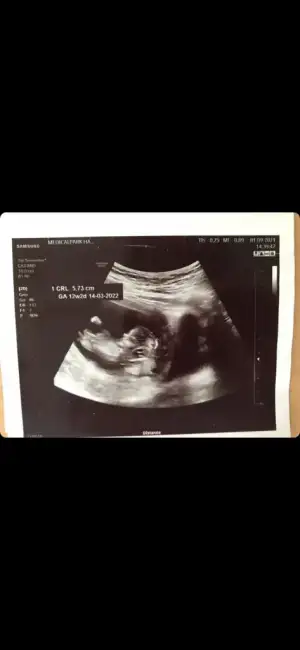

Merhaba kizlar 12+1 iz doktor %90 bir oran verdi ama siz ne dersiniz teoriye göre?

• IMG-20210916-WA0004.webp

IMG-20210916-WA0004.webp

23,2 KB · Görüntüleme: 96